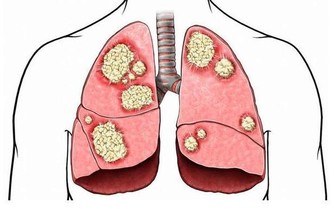

此外,需要注意的是,這4類指標出現異常的人,容易得老年癡呆:同型半胱氨酸、甲狀腺功能、血糖、血脂。